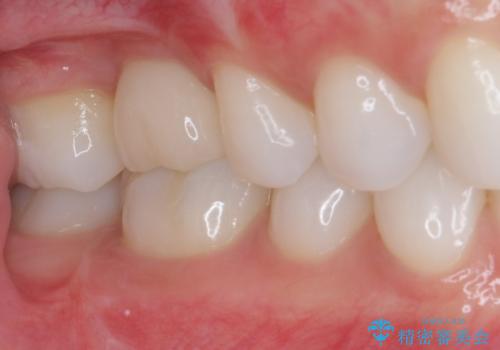

放置した奥歯の虫歯 インプラントによる欠損補綴治療

- 歯がほとんどなくなってしまうまで虫歯を放置してしまったとのことで来院された患者様です。

抜歯が必要であることは患者様自身も理解されており、インプラントによる欠損補綴治療を希望されていらっしゃいました。

虫歯を放置した期間が長かったため、対合の下顎大臼歯が上顎に迫ってきており、咬み合わせは非常にシビアでした。

仮歯装着中に頻繁に脱離したため、オールセラミッククラウンは脱離の少ないスクリュータイプとしました。